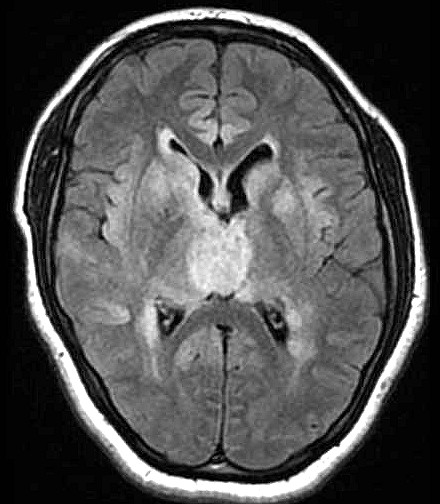

| Fem. 17a. |

| Nódulo sólido homogêneo preenchendo o III ventrículo, com limites precisos, com hipossinal em T1 e hipersinal em T2 e FLAIR, que se impregna por contraste paramagnético. Lesão menor implantada no assoalho do IV ventrículo provavelmente representa disseminação por via liquórica. |

| F. 17a. Tumor teratóide rabdóide atípico de III ventrículo. RM | HE | VIM, GFAP | HHF35, desmina, 1A4 | AE1AE3, EMA |